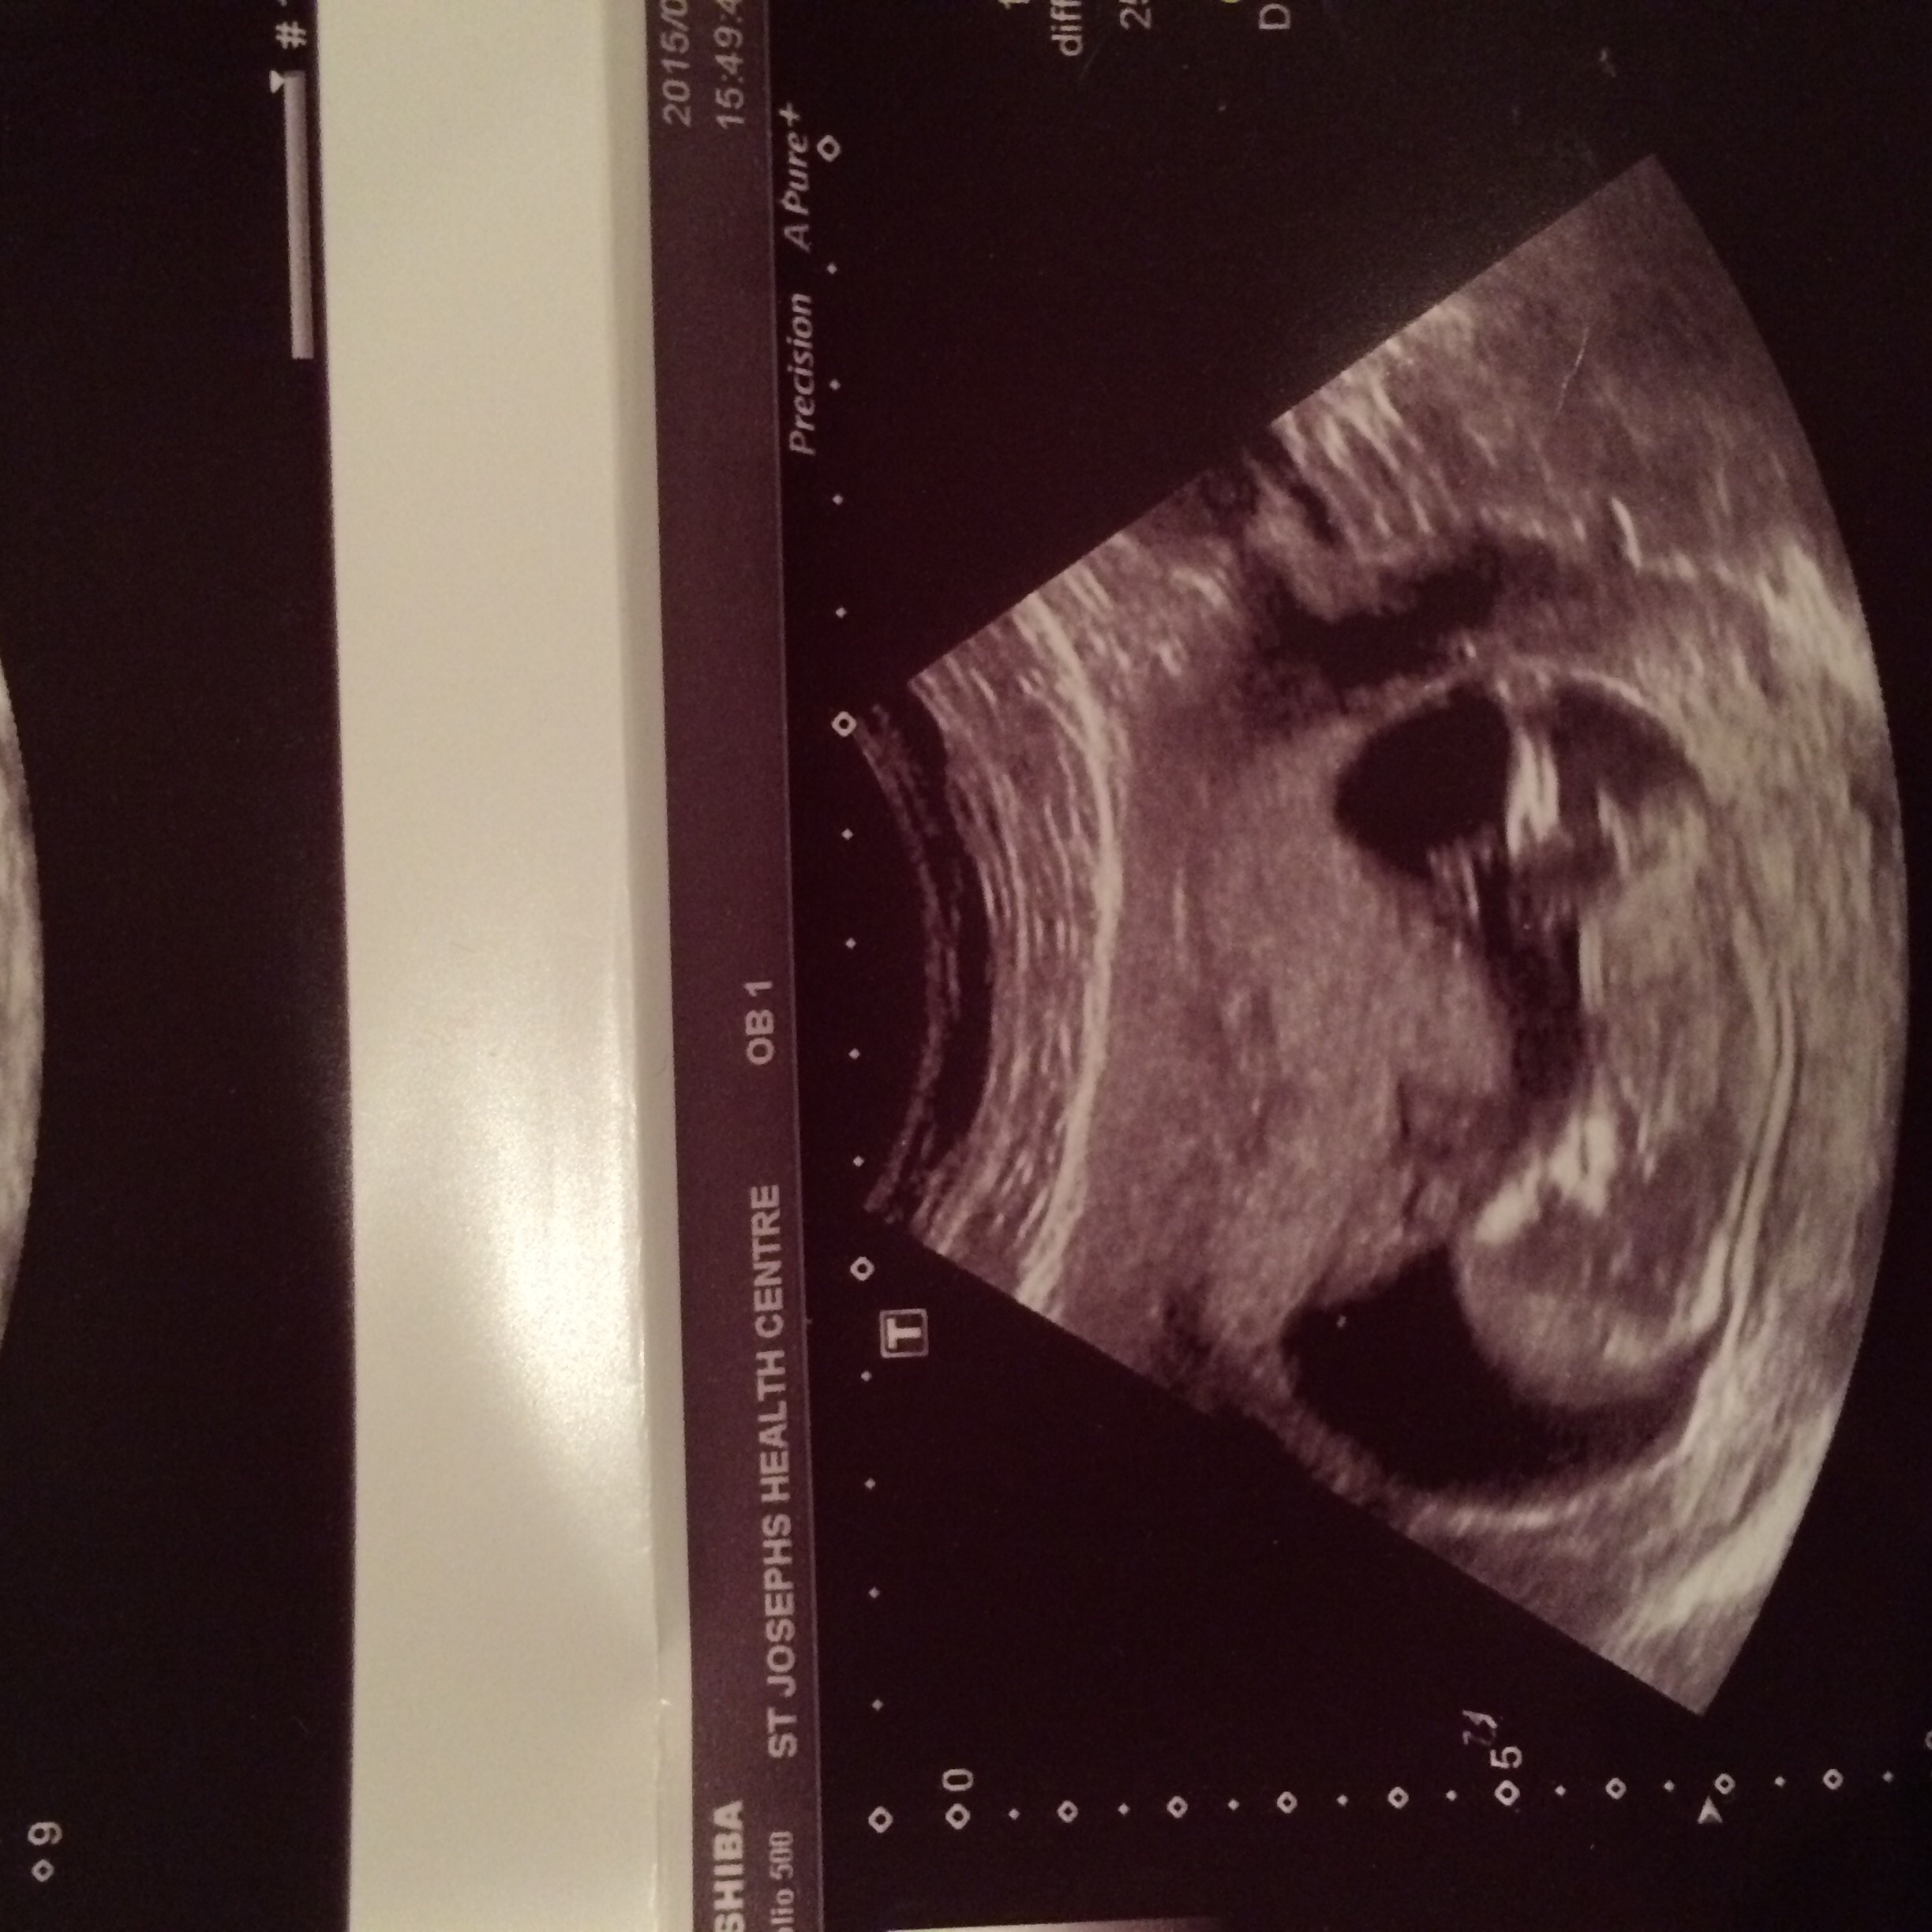

12w6dAttachment 27290:DS:Attachment 27291

These are all same baby lol between 12-12/6